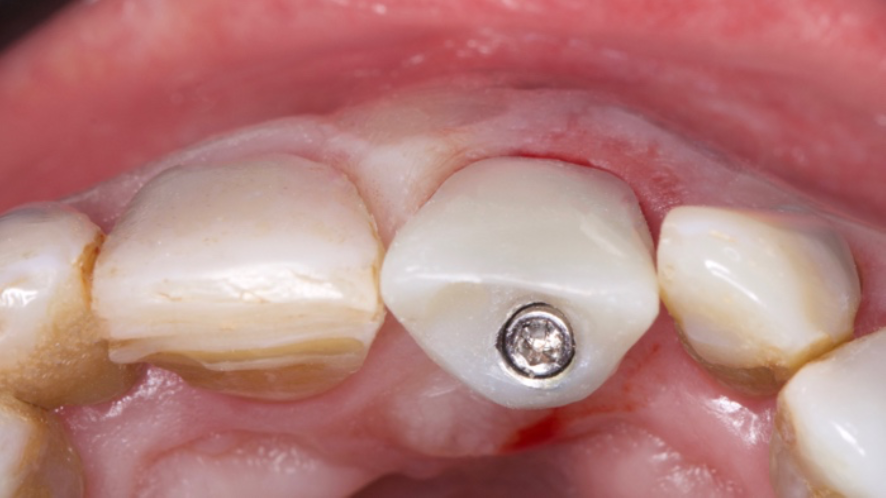

O objetivo deste relato de caso é mostrar a utilização do implante de diâmetro reduzido em região anterior de maxila com limitação óssea, respeitando a anatomia do processo alveolar e consequentemente utilizando um componente angulado para corrigir a posição da saída do parafuso para confecção de uma prótese aparafusada.

Conforme discutido na literatura, a colocação imediata de implantes na zona estética requer que o clínico tenha conhecimento e experiência em diversas áreas. Isso inclui diagnóstico estético, técnicas de extração minimamente invasivas, procedimentos cirúrgicos plásticos orais (por exemplo, enxerto de tecidos duros e moles) e colocação de implantes tridimensionais (3D) precisos com o uso de um implante mais estreito (3,3 mm a 4,3 mm), o que garante um espaço vestibular de pelo menos 2 a 3 mm adjacente à parede do alvéolo bucal intacto. Isso pode ser pré-planejado com uma análise cuidadosa através de exames de imagem para uma melhor compreensão do plano restaurador. O uso de técnicas avançadas de imagem, como a tomografia computadorizada de feixe cônico (CBCT), pode auxiliar no planejamento preciso do tratamento e na colocação do implante.

O planejamento no tratamento de implante imediato deve incluir uma avaliaçãocompleta do alvéolo de extração, osso circundante e tecidos moles. Essa avaliação ajuda a determinar o tamanho, o tipo e a técnica de colocação do implante.